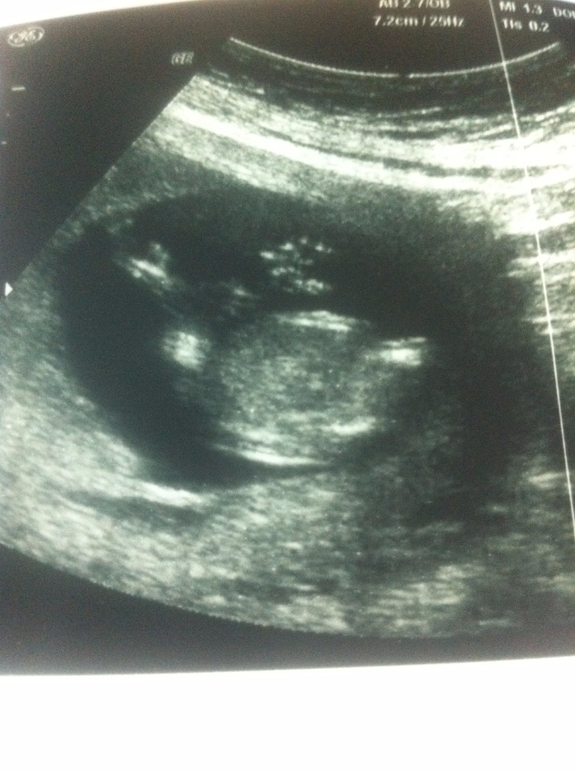

Под катом фото, гляньте плиз...Я вот полового бугорка тоже не увидела вообще.

я вот тоже думаю, если бы мальчик был, то врач хотя бы предположила))

Мария

Я тоже девочку вижу, по форме головы. Я делала узи в 12 недель дали фото с узи, сидела рассматривала и сделала вывод, что по строению головы похож на мальчика, на 19 неделе подтвердили что мальчик)))))

А как по голове вам определили? Я вот по голове смотрела и прям на девочку похожа была , но в 16 недель мальчика предположили.